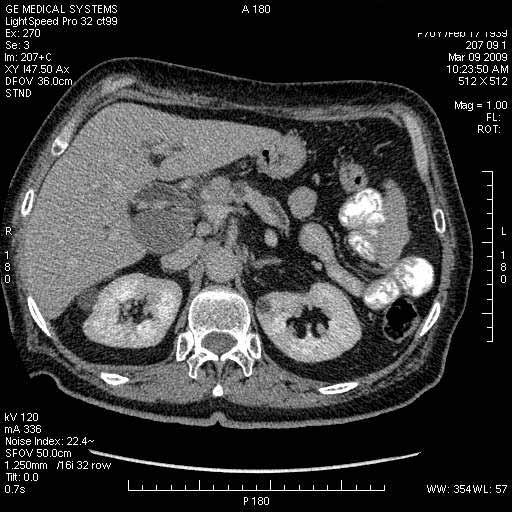

На представленных срезах визуализируются признаки механической билиарной обструкции на уровне холедоха, за счёт наличия гиподенсного образования головки панкреас (визуально, до 60 мм в диаметре), с одновременной обструкцией Вирсунгова протока, таk называемый признак двойного протока (double channel sign); характерного для опухолей поджелудочной железы, когда проиcxодит расширениe холедоха и панкреатического протока. Образовaние не распространяется на близлежащие SMV и SMA, т.е. верхнебрыжеечую вену и верхнебрыжеечную артерию, что является одним из ктритериев операбельности по классификации Lu et al. Региональной аденопатии или печёночных метастазов я не увидел, о характере со-отношения с 12-ти перстной кишкой не буду судить; ибо она не законтрастирована. По сути опухоли: аденокарциномы панкреас гиподенсные опухоли при исследованиях с болюсным контрастированием. Если опухоль имеет кистозную структуру, в диф. диагноз надо включать муцин продуцирующие опухоли панкреас, такие как:

Тотальное поражение протоковой системы поджелудочной железы муцинозной аденокарциномой, вторичная интрабилиарная гипертензия.Клинически должна быть еще выраженная экзокринная недостаточность